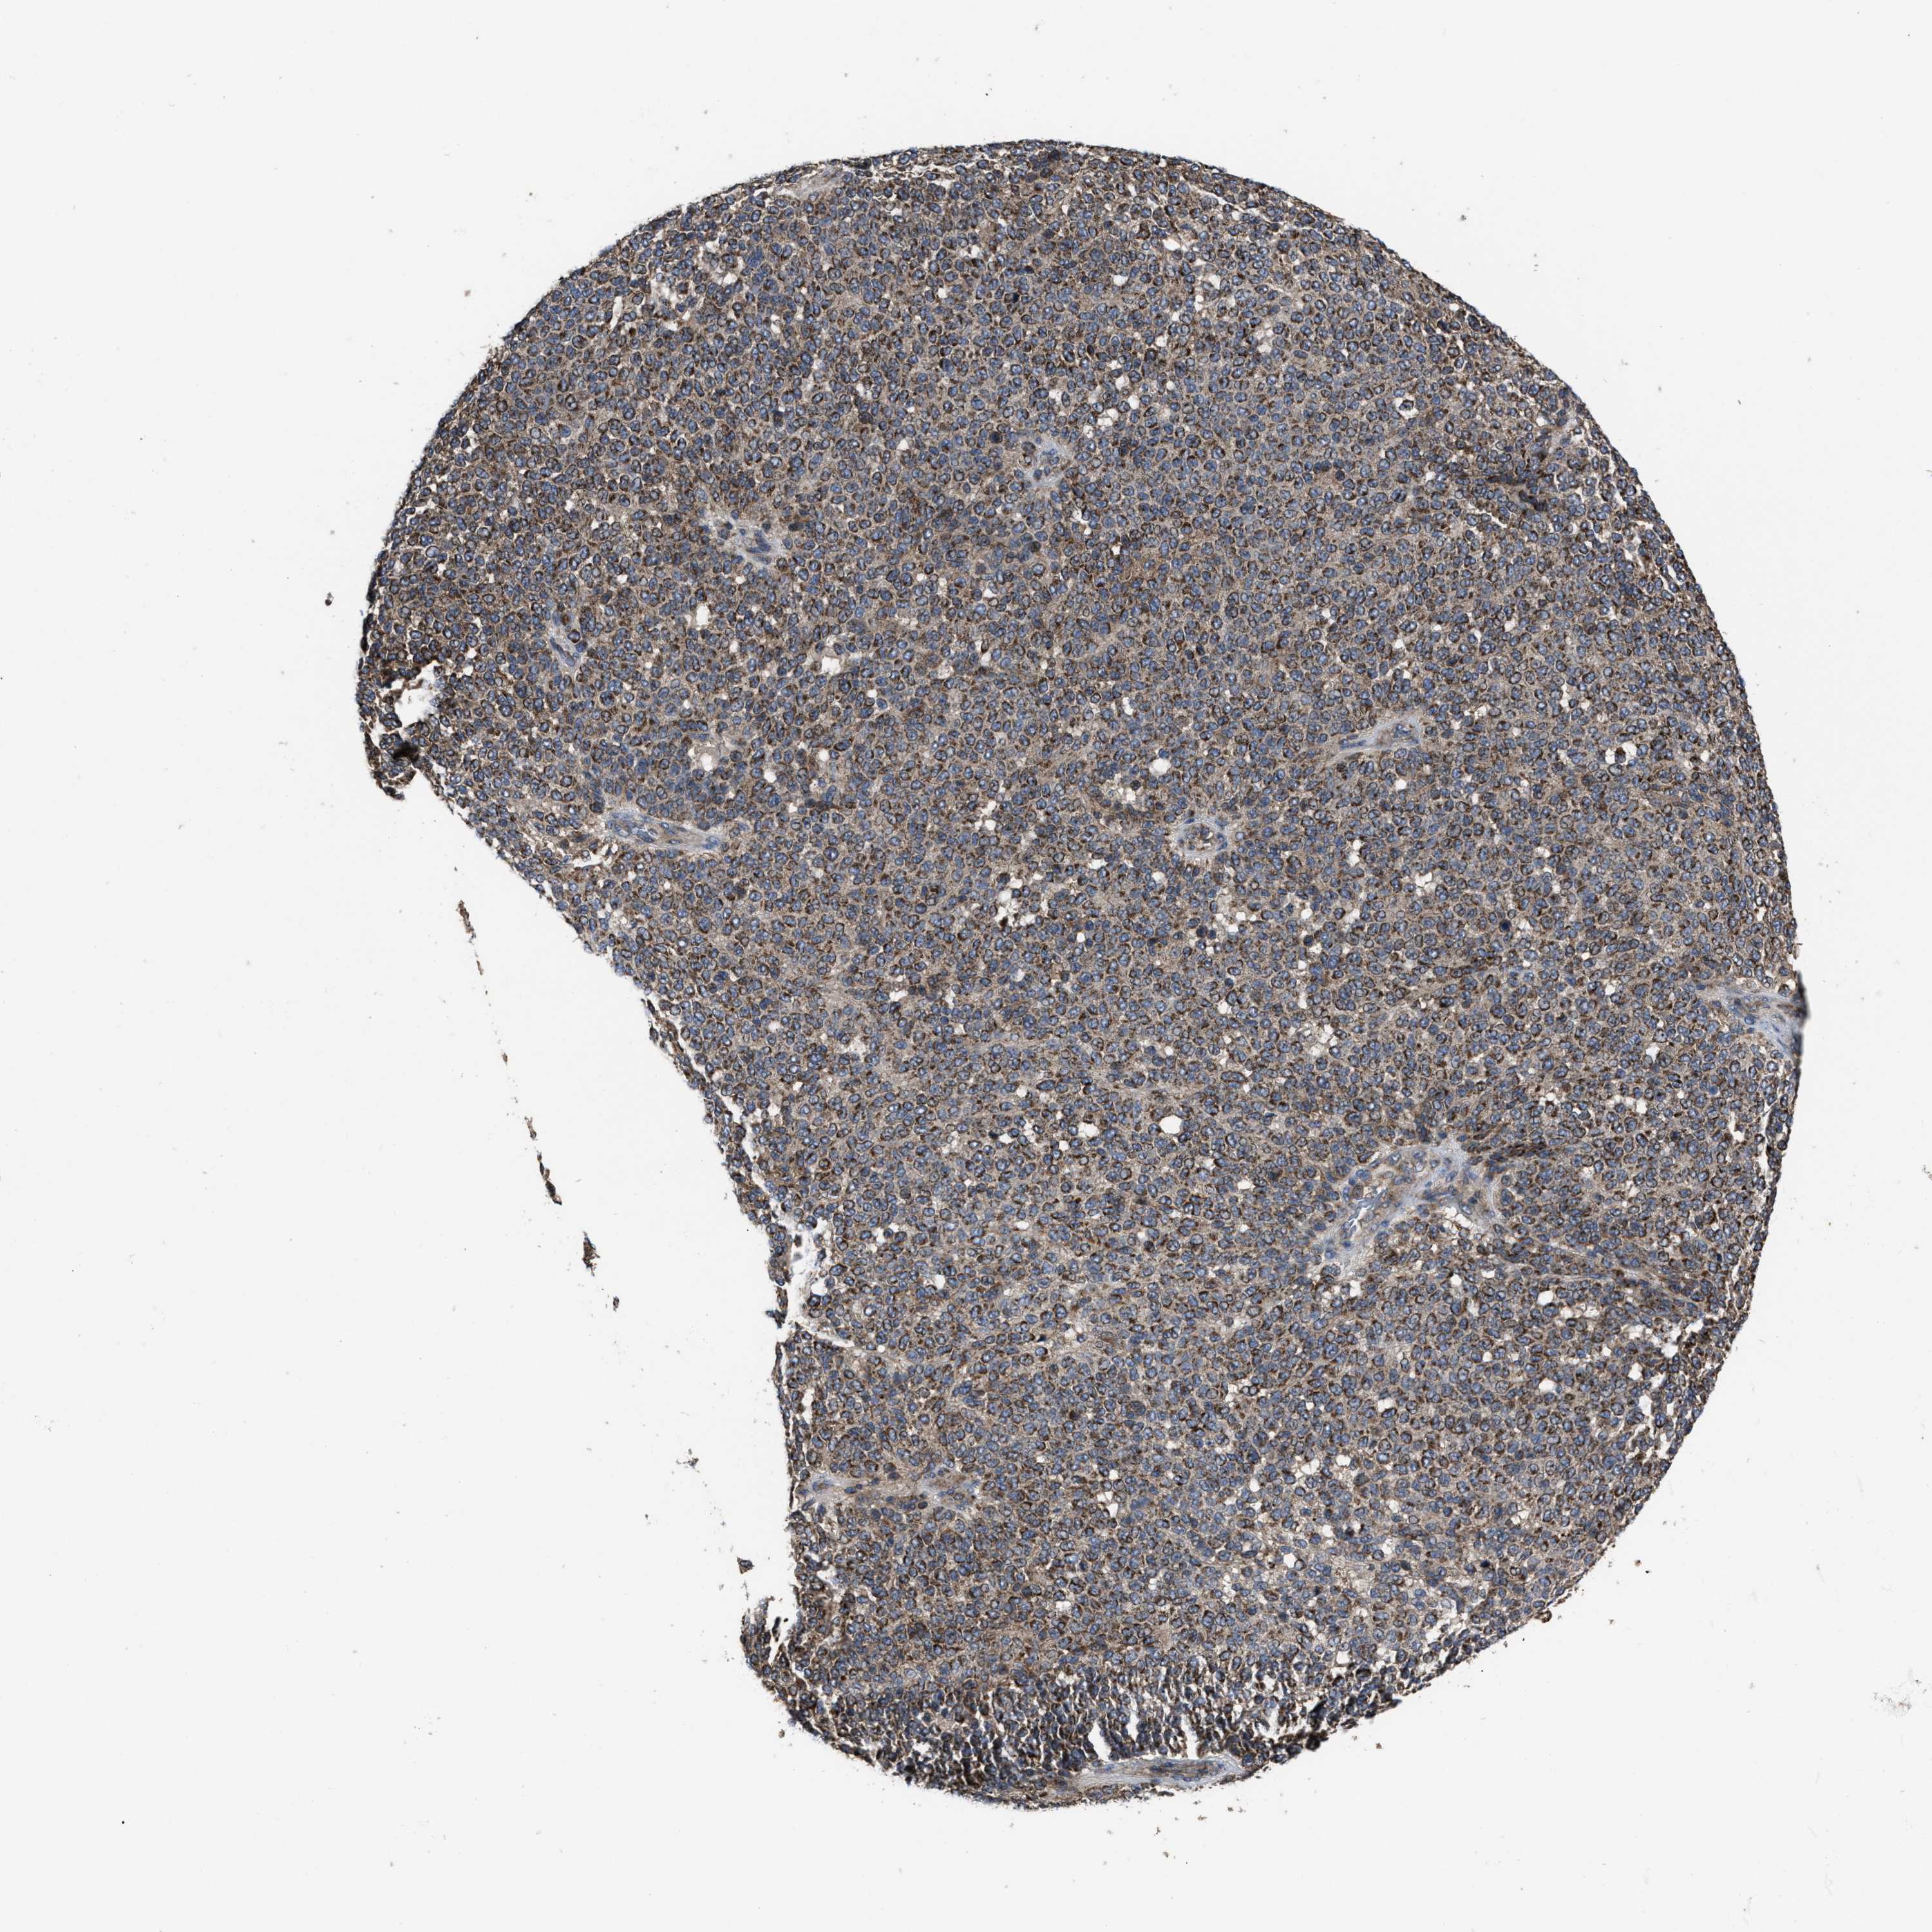

MELANOMA - Protein expressioni

A mouse-over function shows sample information and annotation data. Click on an image to view it in a full screen mode. Samples can be filtered based on level of antibody staining by selecting one or several of the following categories: high, medium, low and not detected. The assay and annotation is described here.

Note that samples used for immunohistochemistry by the Human Protein Atlas do not correspond to samples in the TCGA dataset.

Antibody stainingi

Antibody staining in the annotated cell types in the current human tissue is reported as not detected, low, medium, or high, based on conventional immunohistochemistry profiling in selected tissues. This score is based on the combination of the staining intensity and fraction of stained cells.

Each image is clickable and will lead to virtual microscopy that enables deeper exploration of all samples and also displays staining intensity scores, fraction scores and subcellular localization as well as patient and tissue information for each sample.

Antibody HPA016450

Antibody HPA021079

Staining

High

Medium

Low

Not detected

Intensity

Strong

Moderate

Weak

Negative

Quantity

>75%

75%-25%

<25%

None

Location

Nuclear

Cytoplasmic/membranous

Cytoplasmic/membranous,nuclear

Malignant melanoma, NOS

Malignant melanoma, Metastatic site